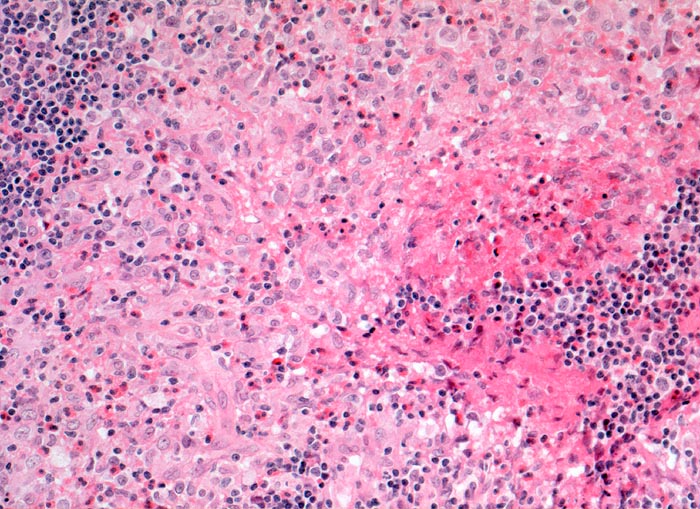

- CD1a wird von einer Reihe von Antigen-präsentierenden Zellen exprimiert. Unter anderem Langerhanszellen und interdigitierende Reticulumzellen. 70% aller Thymozyten sind CD1a positiv, nicht aber frühe Thymozyten oder ausgereiften Thymozyten

- Precursor T-ALL positiv. Post thymische T-CLL, Sezary Syndrom, kutanes T-Zell Lymphom und nodale T-Zell Lymphome negativ.

- Identifikation einer Langerhanszellhistiozytose.

CD1a ist positiv in kortikalen Thymomen.